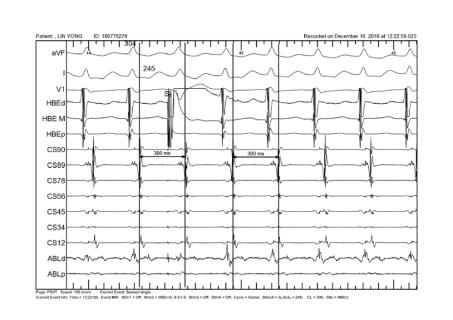

<p>图中电生理现象&#xff0c;提示该心动过速为&#xff1f;</p>

图中电生理现象,提示该心动过速为?

AVNRT

AT

PJRT

ILVT

<p>对于图片中Para His pacing的过程&#xff0c;描述正确的是&#xff1f;&#xff08;多选&#xff09;</p>

对于图片中Para His pacing的过程,描述正确的是?(多选)

逆传路径为AP

第一跳夺获了HIS

逆传路径为AVN

第二跳夺获了HIS